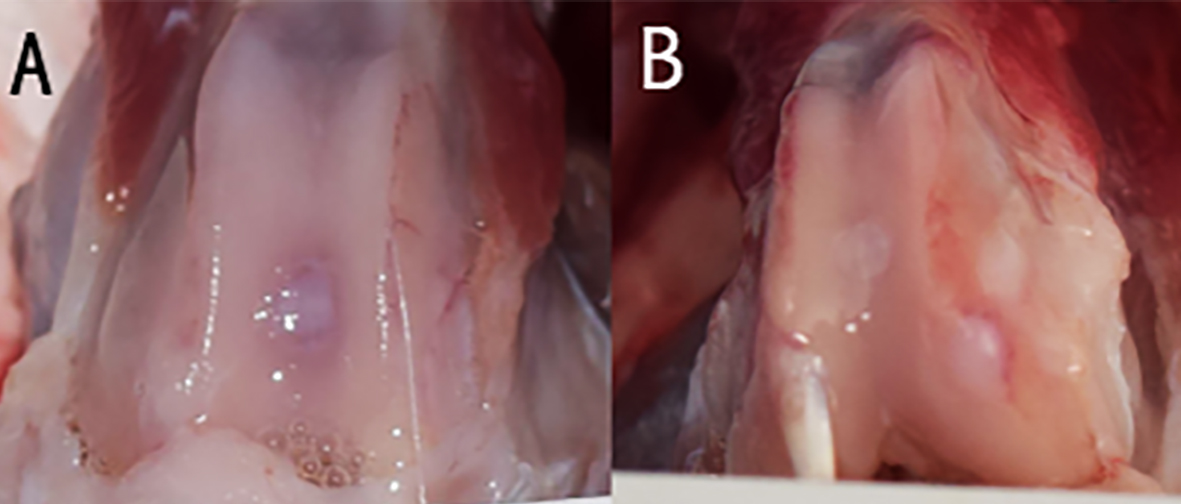

En un estudio sobre el CPG (en prensa), este mismo hidrogel, ha tenido resultados prometedores para reparar lesiones condrales críticas e inducidas de 3 mm en conejos blancos adultos de Nueva Zelandia. El grupo tratado con hidrogel obtuvo mejor condrogénesis y se integró parcialmente al cartílago adyacente a los 6 meses (Figura 3) (Figura 4). Además, el hidrogel puede ser formado creando múltiples capas que reproducen capas nativas de tejidos que serán regeneradas en las lesiones osteocondrales combinadas. Previamente hemos demostrado una secuencia simple de fotopolimerización usando una versión estable, es decir no degradable, de hidrogeles a base de PEG cambiando el tipo y concentración de análogos de MEC, como también la rigidez local dentro de cada capa. Notablemente, bajo carga compresiva, la variación en la rigidez del hidrogel dentro de cada capa produjo alta tensión en la capa blanda (similar al cartílago símil), baja tensión en la capa rígida (similar al hueso) y tensión moderada en la interfaz. Esto permitió la posibilidad de dirigir la diferenciación de células madre embebidas en el hidrogel (47). En vista a tratar lesiones complejas que involucran distintos tejidos, es posible combinar diferentes nichos de células madre e hidrogeles para guiarlas hacia la diferenciación deseada.